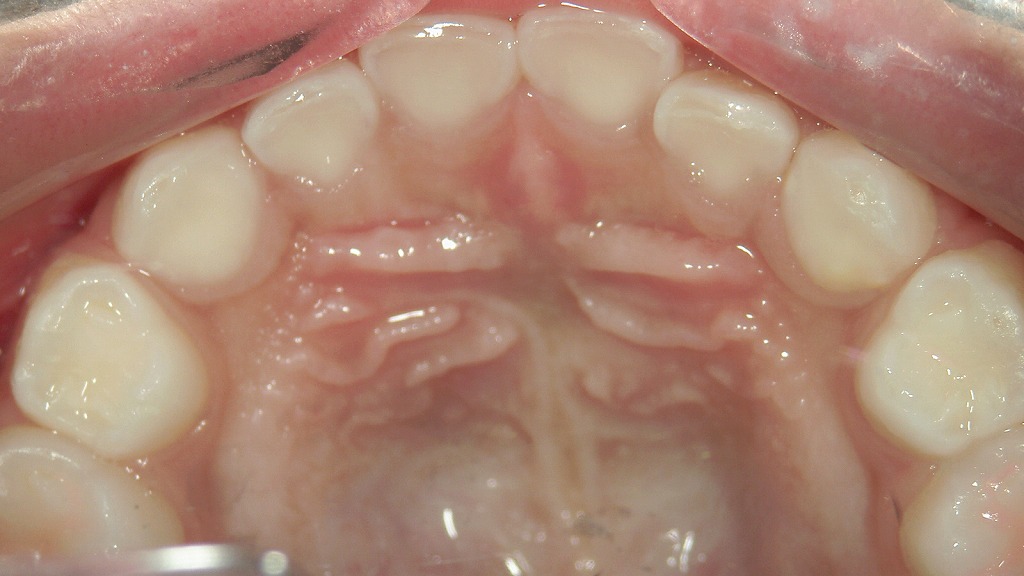

📷霊長空隙が存在する症例

乳歯の歯と歯の間にほとんど隙間がなく、全体的にキュッと詰まっている状態が確認できます。

本来、乳歯の時期は永久歯が大きくなるスペースを確保するために、**歯と歯の間に自然なすき間(霊長空隙・発育空隙)があるのが理想です。

この症例のように隙間がない場合、永久歯が生えてくる際に歯並びがガタつきやすい(叢生になりやすい)**傾向があります。